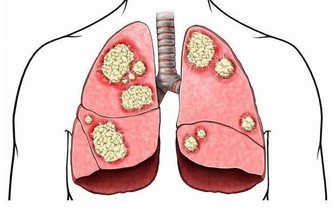

壹週刊報導,台大醫院新竹分院皮膚科醫師邱顯鎰表示,乾癬是一種自體免疫疾病,

患者如果感冒、壓力大,或生活上遇重大事件發生時,就容易誘發乾癬發作。

一般民眾如有以下症狀,也要當心罹患乾癬,

若確診建議趕緊就醫治療,可服用免疫製劑或施打生物製劑減緩發炎反應。